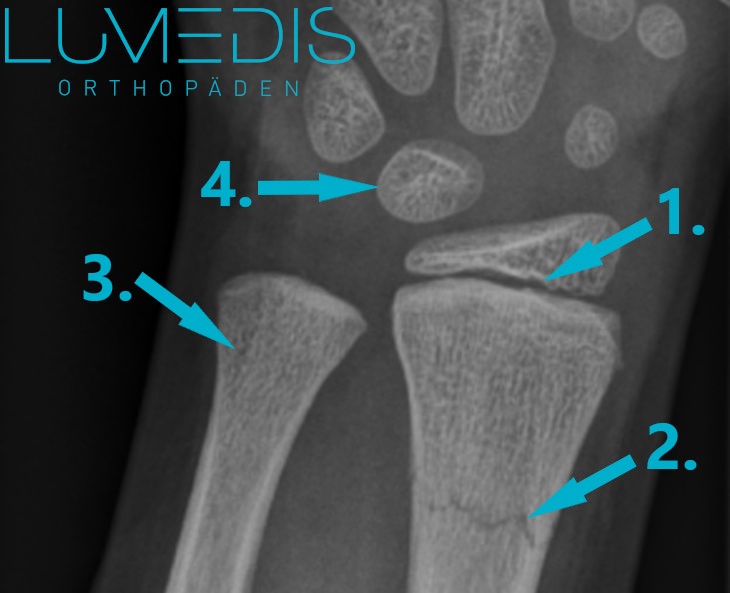

Röntgenbild eines Wulstbruchs der Speiche